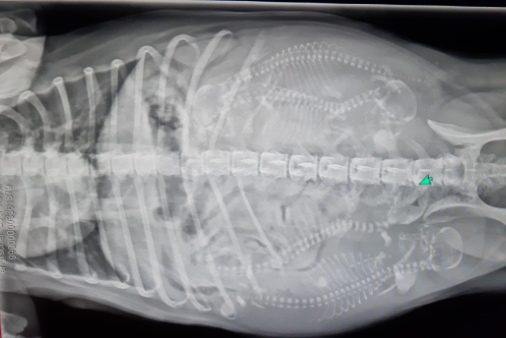

23.02.2021 - heute ist der 58. Tag und wir fahren endlich

| Immer

Fabrice - |

Blutabnahme für die genetischen Untersuchungen, HD -

| nun

gewehrt, |

schwupps lag sie auf dem Rücken. Das erste Bild war etwas

| auf dem

hatte ich |

oder 6 damit die Wahrscheinlichkeit auf ein schwarzes

|

..... und so war

ich doch etwas enttäuscht, dass es nur 4 sind ;o(( |

| .....

ich hoffe nicht, dass das 4 zobelfarbene Jungs sind ;o(( |